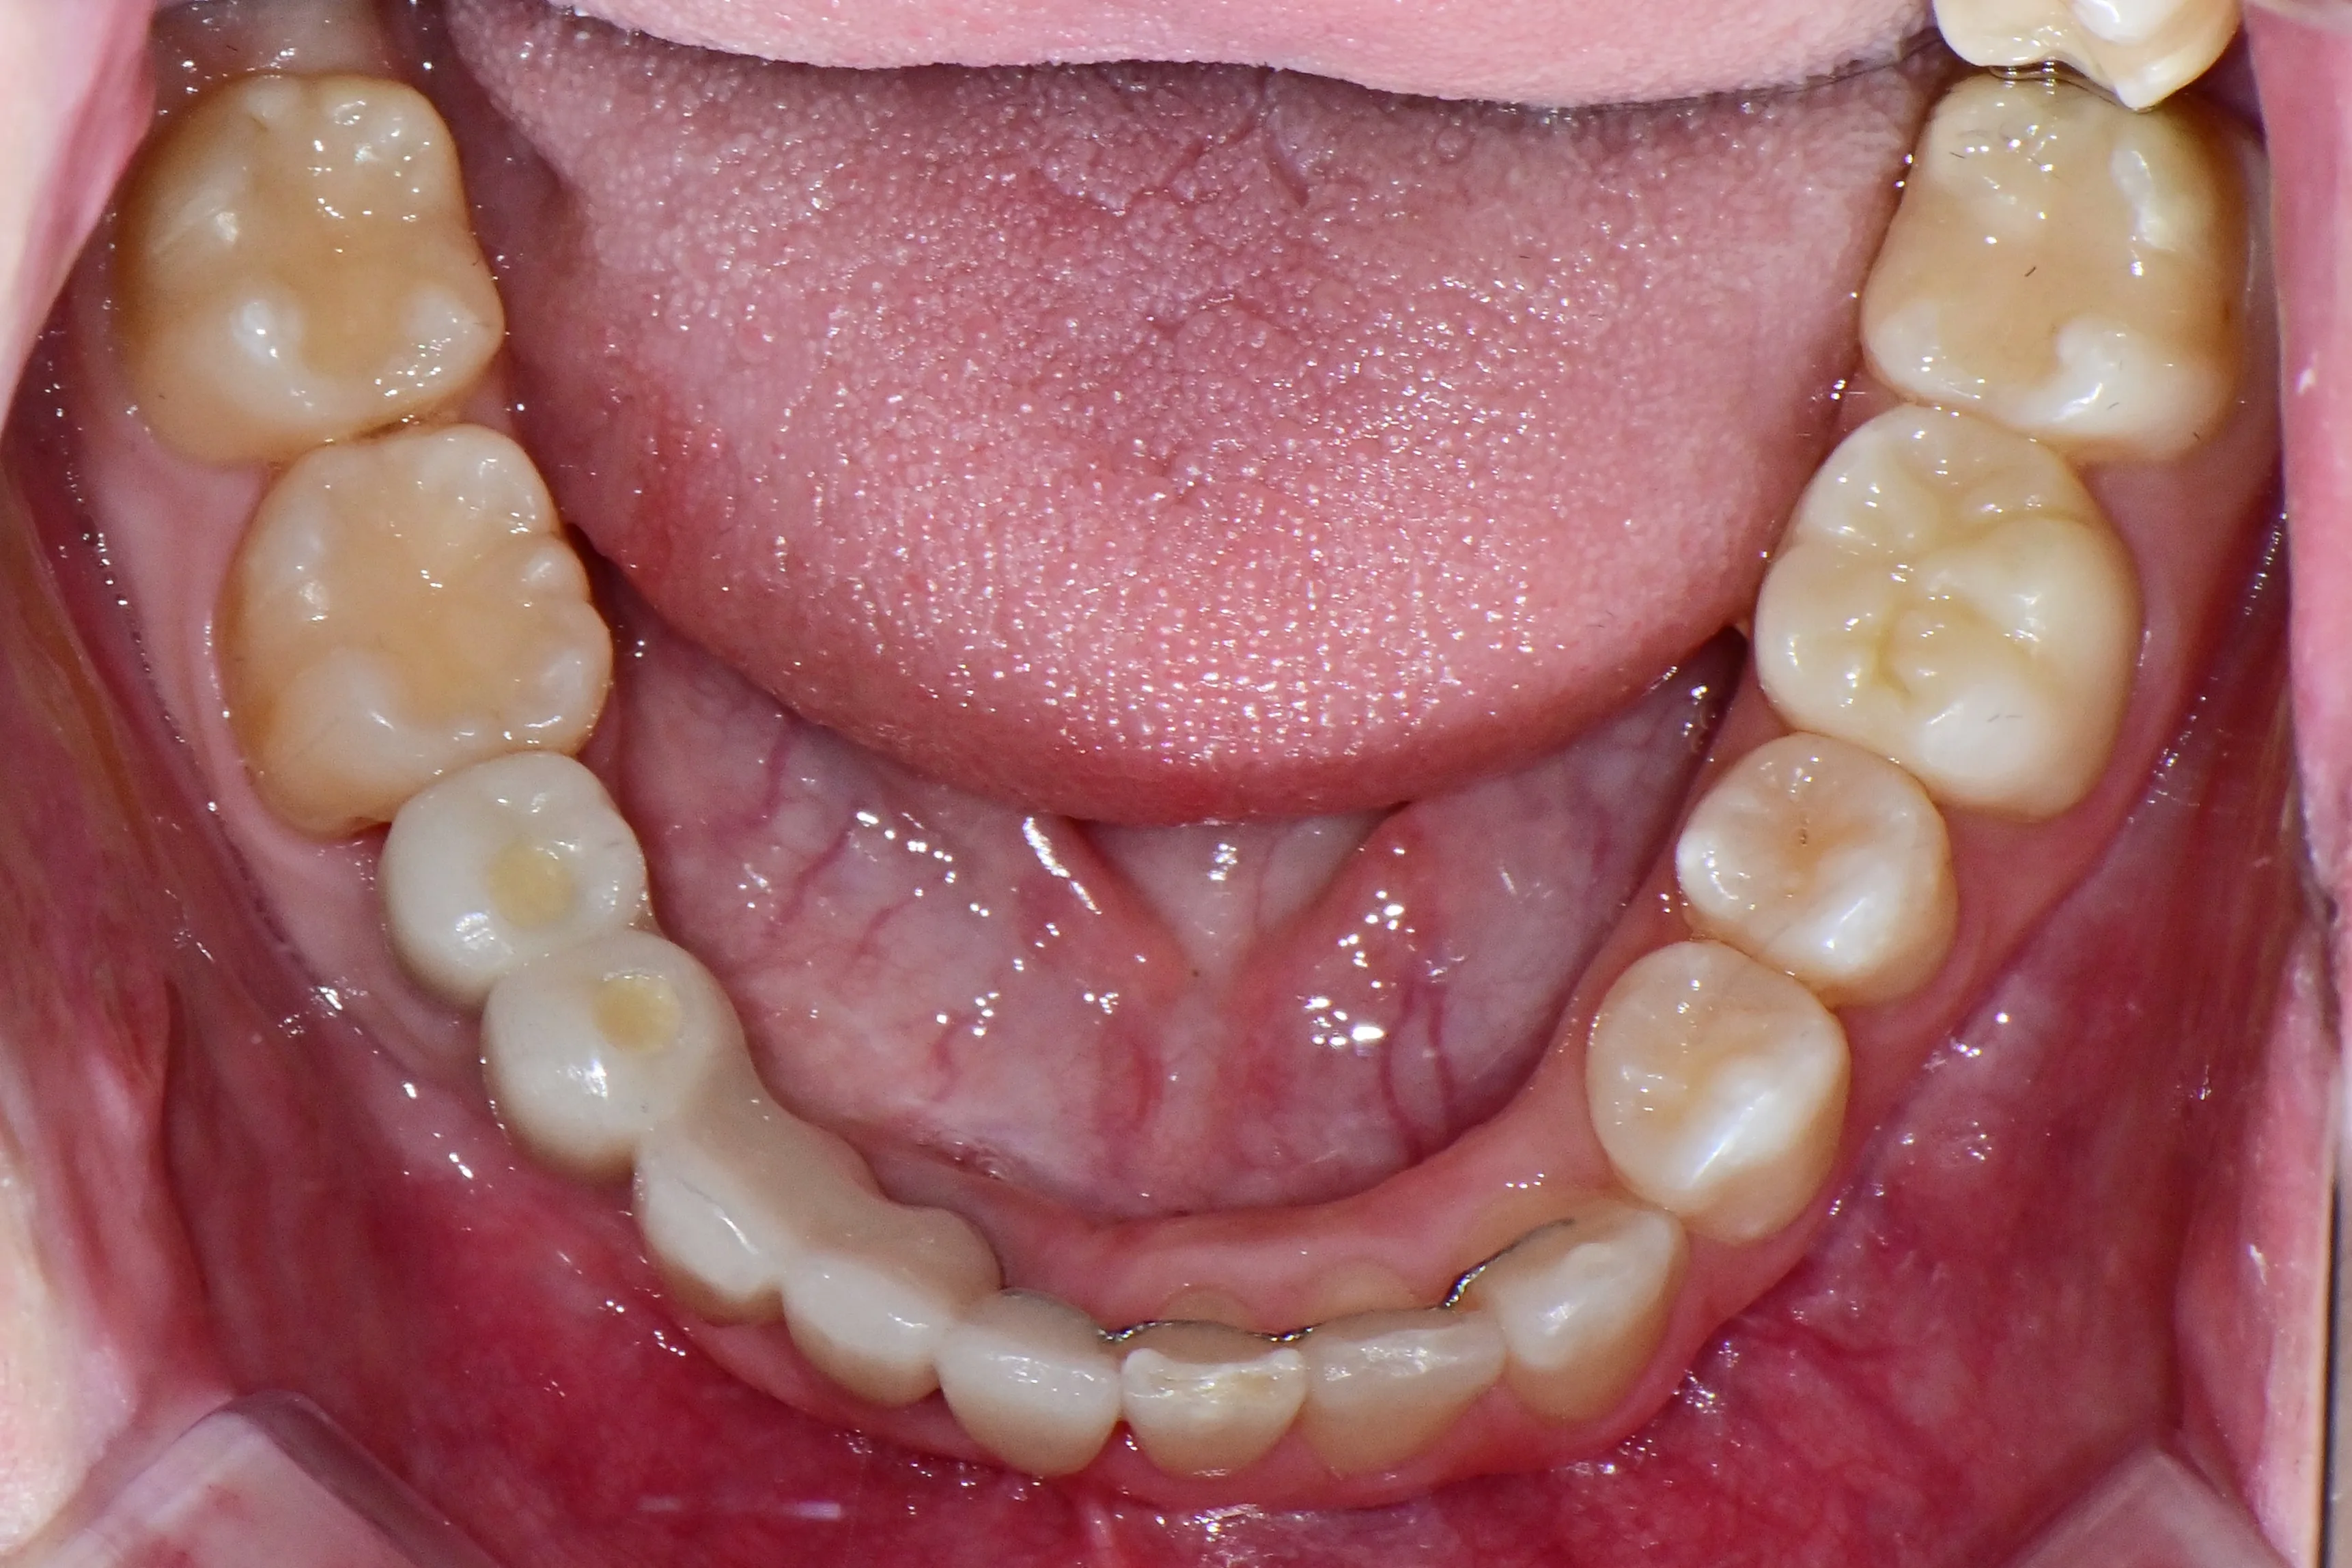

만 21세 환자로, 기존에 사고로 여러 치아를 다치고 상실한 상태로 매우 심한 교합무너짐이 있었습니다.

치료전 (Before)